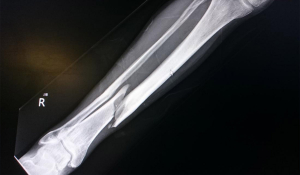

Гомілка - це частина ноги людини від коліна до стопи, яка складається з великої та малогомілкової кісток.

Перелом гомілки може трапитися внаслідок, до прикладу, падіння чи сильного удару.